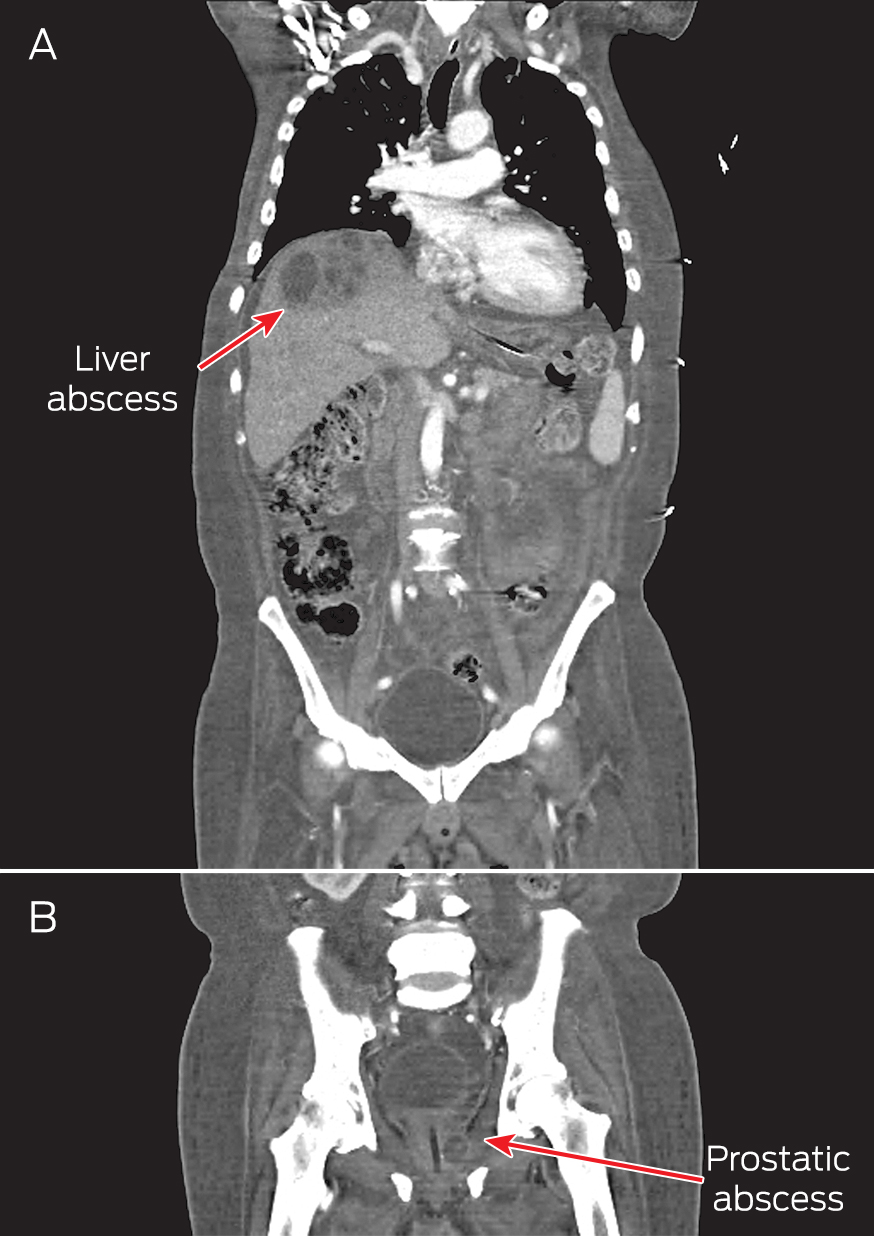

A computed tomography (CT) scan of the thorax, abdomen and pelvis showed right pleural effusion and liver and prostate abscesses (Box). The patient was diagnosed with disseminated melioidosis with multiorgan abscesses, and he was started on intravenous imipenem for a planned duration of 6 weeks. Supportive therapy with intravenous normal saline was instituted to resolve his dehydration. Therapeutic drainage of the liver abscess and right pleural effusion was performed under ultrasound guidance.